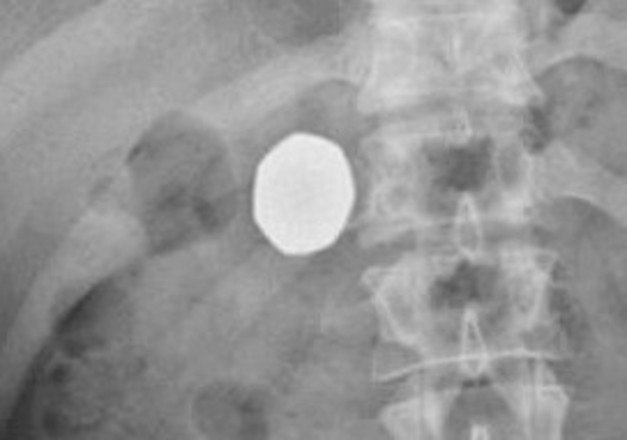

Em novos exames, foi detectado que as moedas ainda estavam no estomago do rapaz. Para piorar, elas haviam passado pela mucosa gástrica, algo que os médicos nunca haviam visto anteriormente

Mesmo assim, o rapaz decidiu esperar para que a moeda seja evacuada naturalmente de seu corpo. Médicos alertaram que os riscos de uma cirurgia seriam maiores do que danos potencialmente causados pela moeda